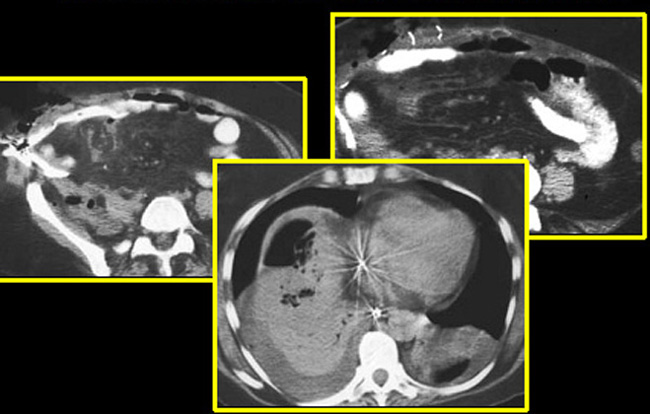

Sub diaphragmatic

Subdiaphragmatic abscess post splenectomy

• Arrow points to multiloculated thick walled fluid collection in the left upper quadrant of the abdomen.

• Note absence of spleen.